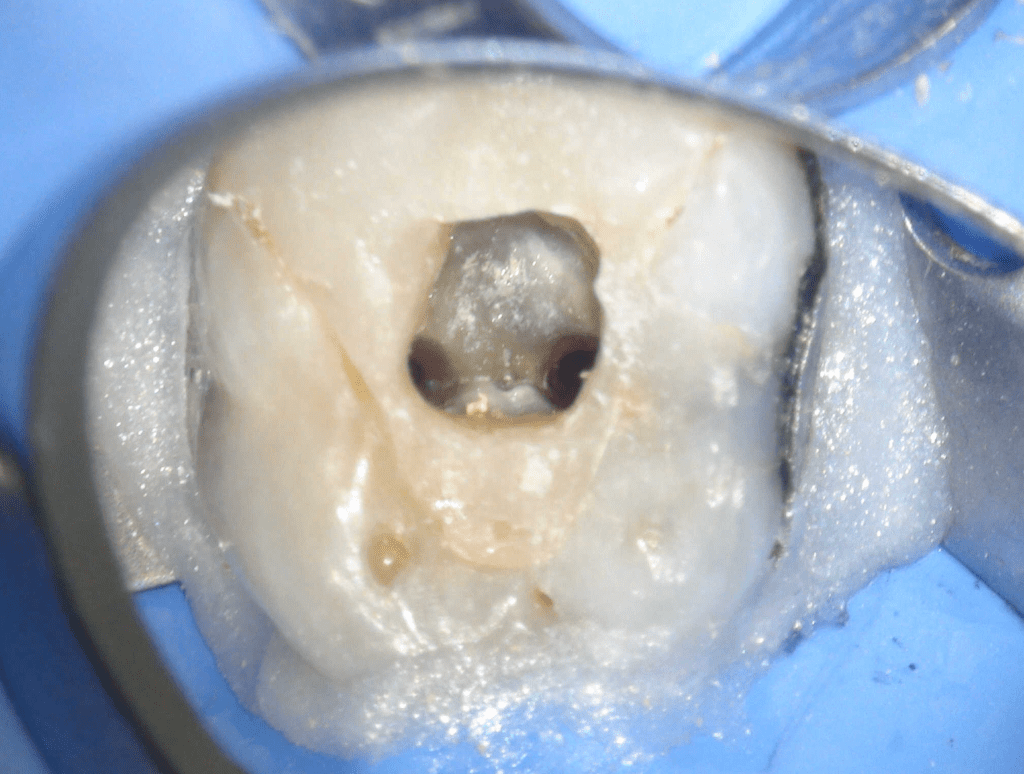

Fisura, remoción amalgama para explorar